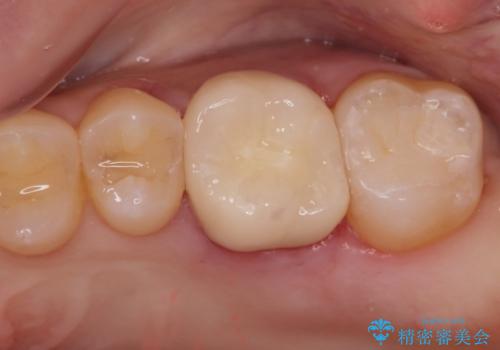

金の詰め物の中にある虫歯を除去してセラミック治療

- 金の詰め物の中が黒く透けていて虫歯があるので拡大鏡下で外し、虫歯がない事を確認した後、被せ物で治療しました。

適合の良いクラウン、詰め物が入りました。

適合が良いことで虫歯の再発のリスクが低くなります。